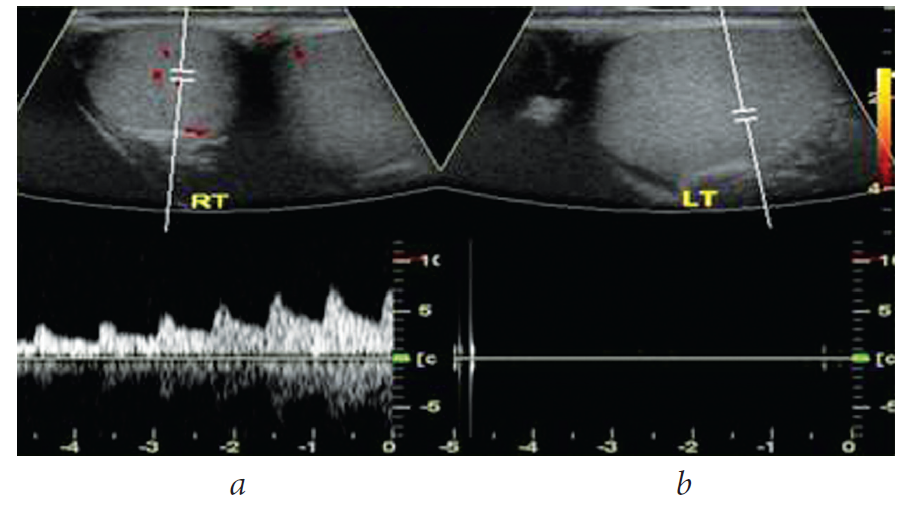

Time from the onset of testicular torsion was <6 h in 8 (22.2%) patients, 6–12 h in 10 (27.8%) patients, 12–24 h in 11 (30.6%) patients, and >24 h in 7 (19.4%) patients. Based on the scrotal Doppler US findings, no blood flow in the testicular artery and a sharp increase in testicle and epididymis size were observed in 28 patients. The other 8 patients showed decreased blood flow in the testicular artery and an increase in epididymis and testicle size (Fig. 2 and 3). In patients with time of onset of testicular torsion <6 h, the decrease in blood flow in the testicular artery was determined by scrotal Doppler US, and incomplete testicular torsion of 180° was observed during the revision of the scrotum. In this case, it was possible to save the testicle and fix it to the tunica of the septum and tunica dartos. In patients with time of onset >12 h, testicular torsion of 360° with insufficient blood flow in the testicular artery, destructive changes in the testicular tissues and epididymis, and signs of hydrocele were detected.

Fig. 3. Patient B., 27 years old. Scrotal Doppler ultrasound before surgery: a – significant blood flow decrease in testicular blood vessels, congestion of testicular tunics, lythic lesion of testicular parenchyma; b – absence of pulsation below torsion

All patients underwent urgent scrotal exploration. During the surgery, 28 (77.7%) patients with pronounced changes in the testicle with no blood flow on Doppler US had signs of necrosis. They underwent orchiepididymectomy (Fig. 4). In 8 (22.2%) patients, the testicle was defined as viable. They underwent reposition and orchidopexy (Fig. 5).

Fig. 4. Patient M., 30 years old, scrotal Doppler ultrasound, absence of pulsation below torsion (a); that testicle during surgery (testicular necrosis), torsion duration more than 24 hours, 360° torsion, orchiepididymectomy was performed (b, c)